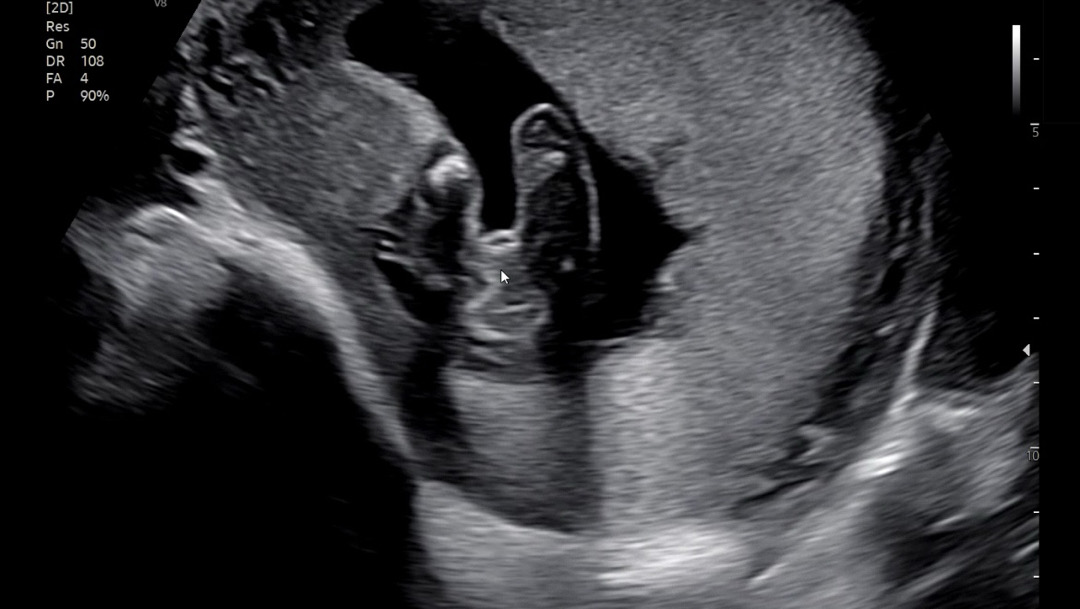

선배맘들 성별 확인부탁드려요🙏🏻🥹

오늘 성별확인하러 갔는데 아기가 가려서 잘안보이네요ㅠㅠㅠ 저 화살표 부분이 아들일까요??

딸같아요 아들은 삼각점이 보인다네요

딸같아요!